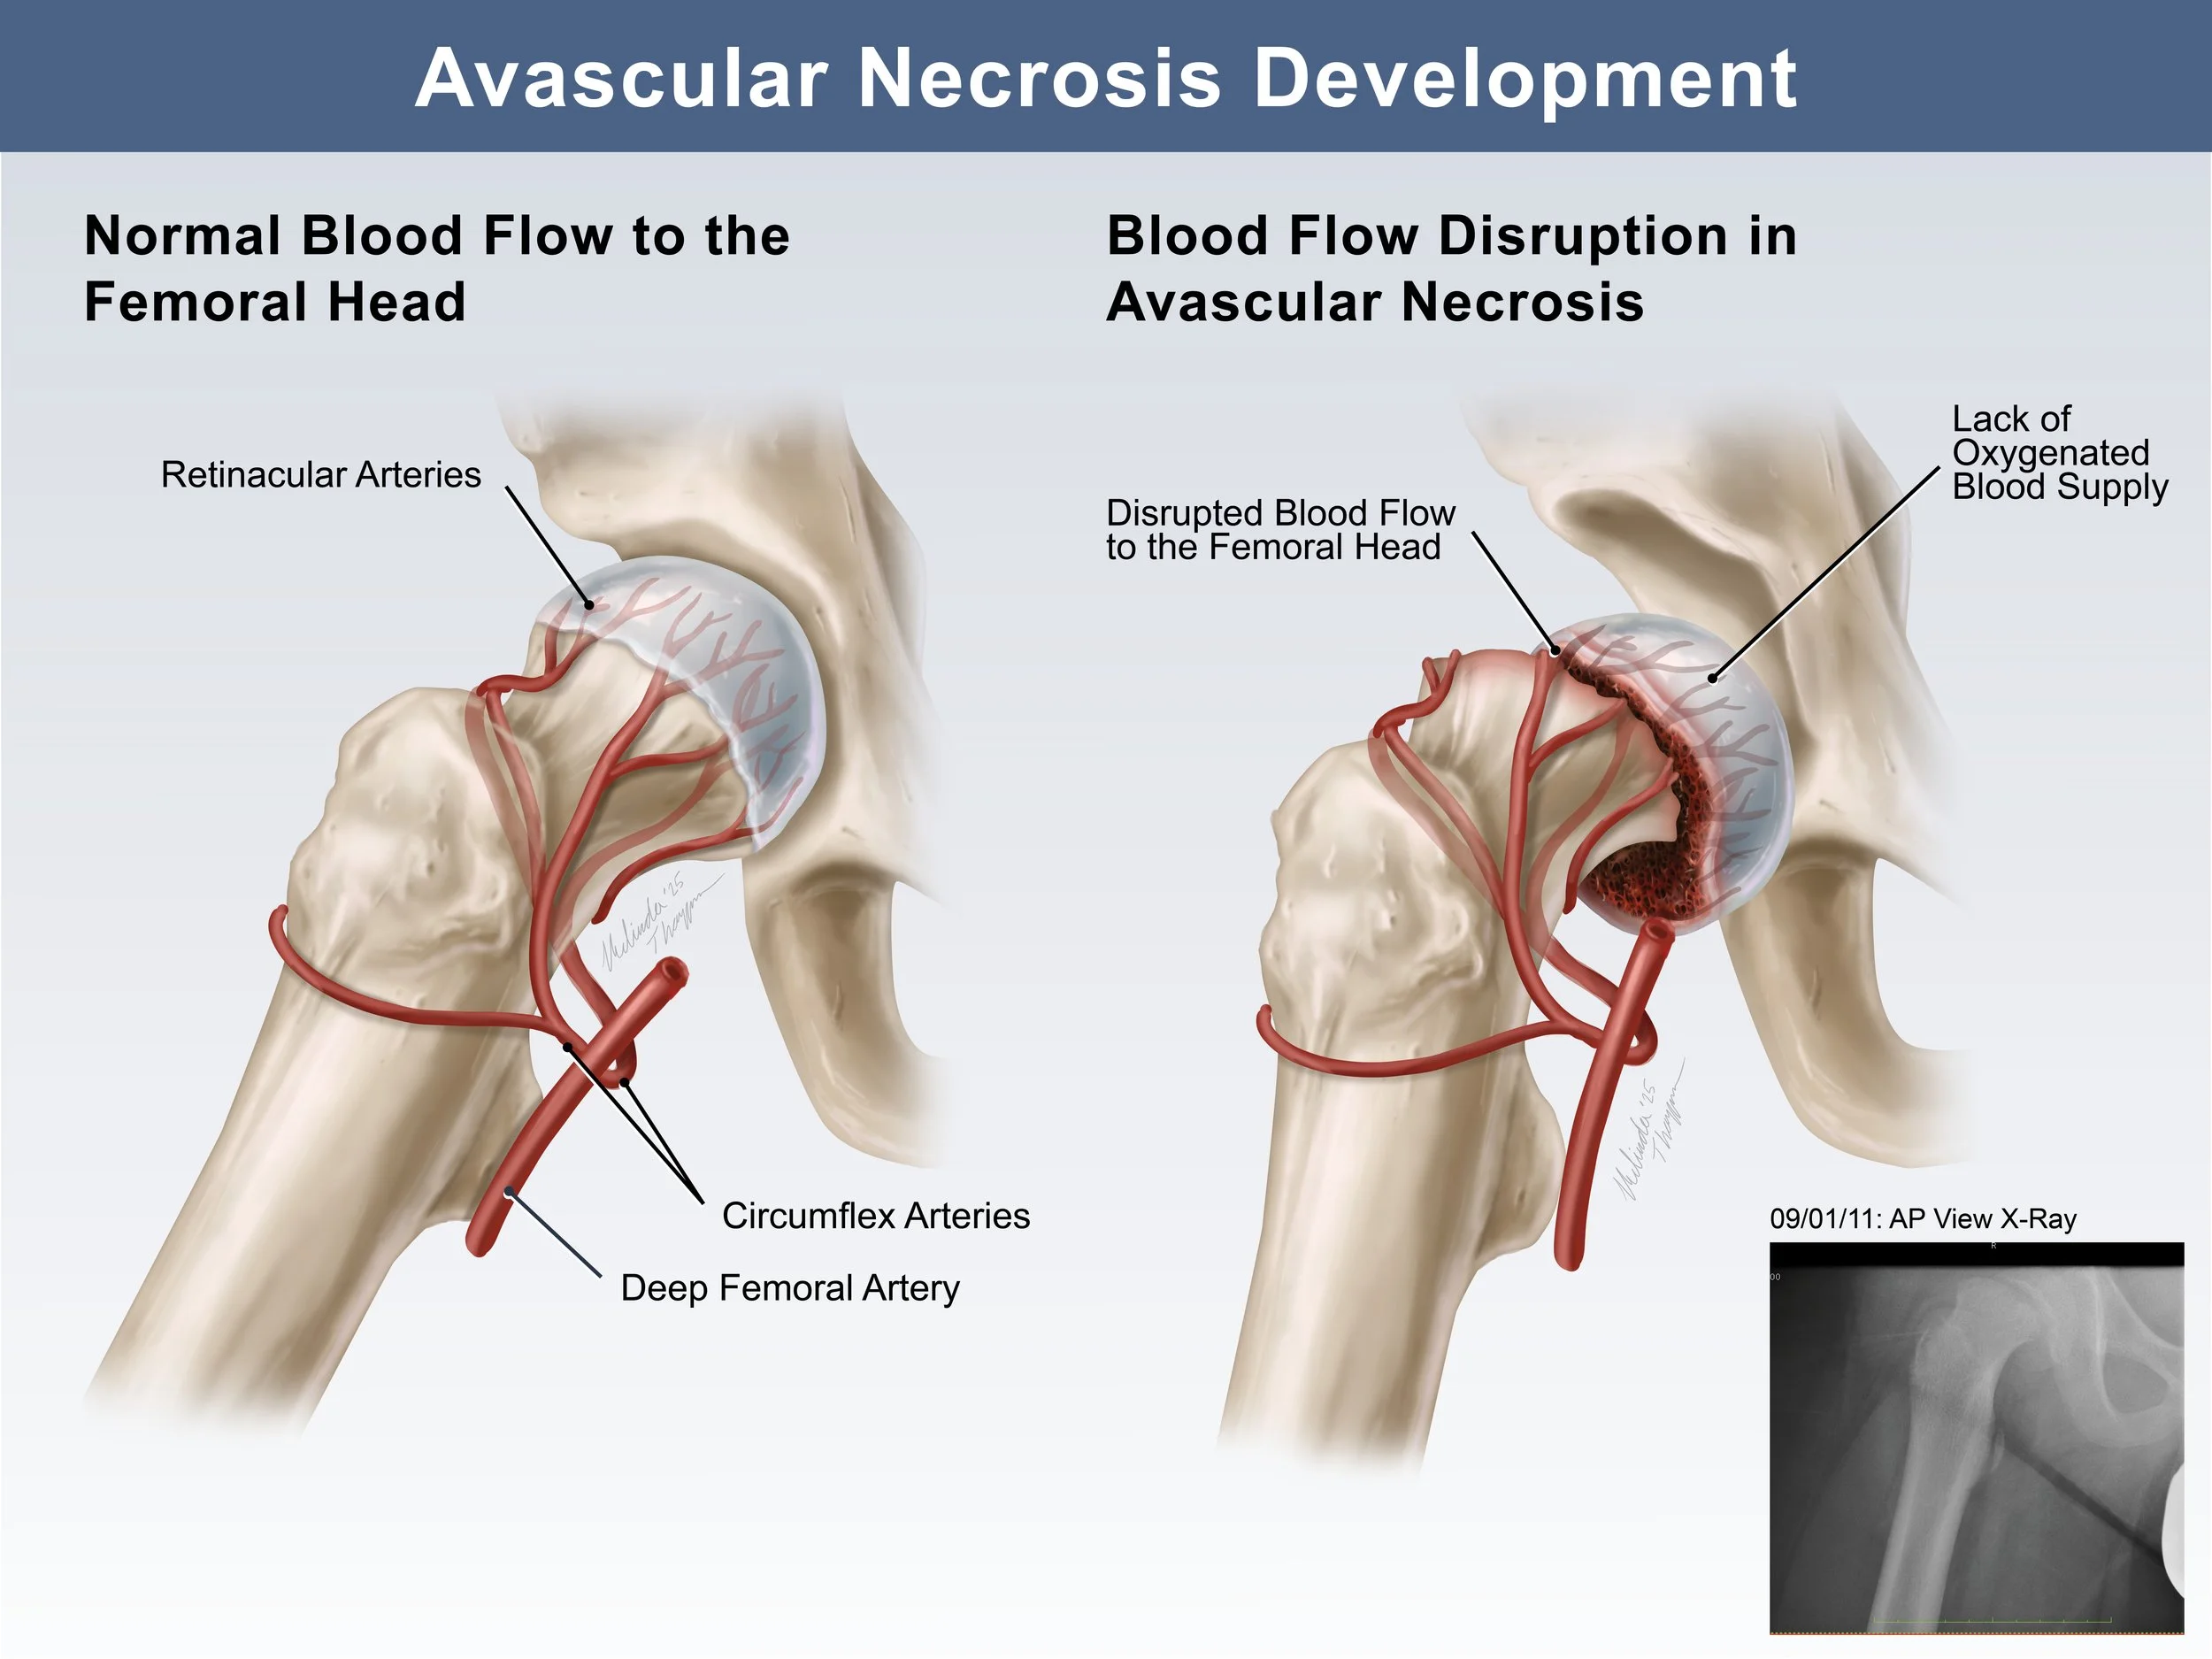

Medical Legal Exhibit: Avascular Necrosis Development in Slipped Capital Femoral Epiphysis Fracture